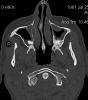

TC exostosis occipital congénica.

TC exostosis occipital congénita.